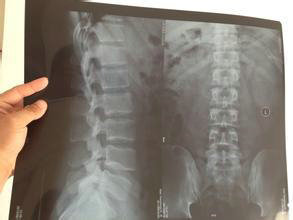

体温36.9℃,不能平躺,枕4年枕头高约32cm,行走困难,胸89.10后凸畸形40度,压痛明显,脊椎侧弯,颌胸距3cm,胸围99cm,呼吸动度0.5cm,腰背部疼痛剧烈夜间常有痛醒,翻身困难,腰椎活动度15度。双髋关节疼痛剧烈,功能明显受限,双膝关节疼痛,双浮髋试验阴性,不能下蹲。

(图:治疗前黄先生后背弯曲变形严重)

诊断为强直性脊柱炎中晚期。

(图:来院复查时弯曲变形的脊柱有了明显的改善)